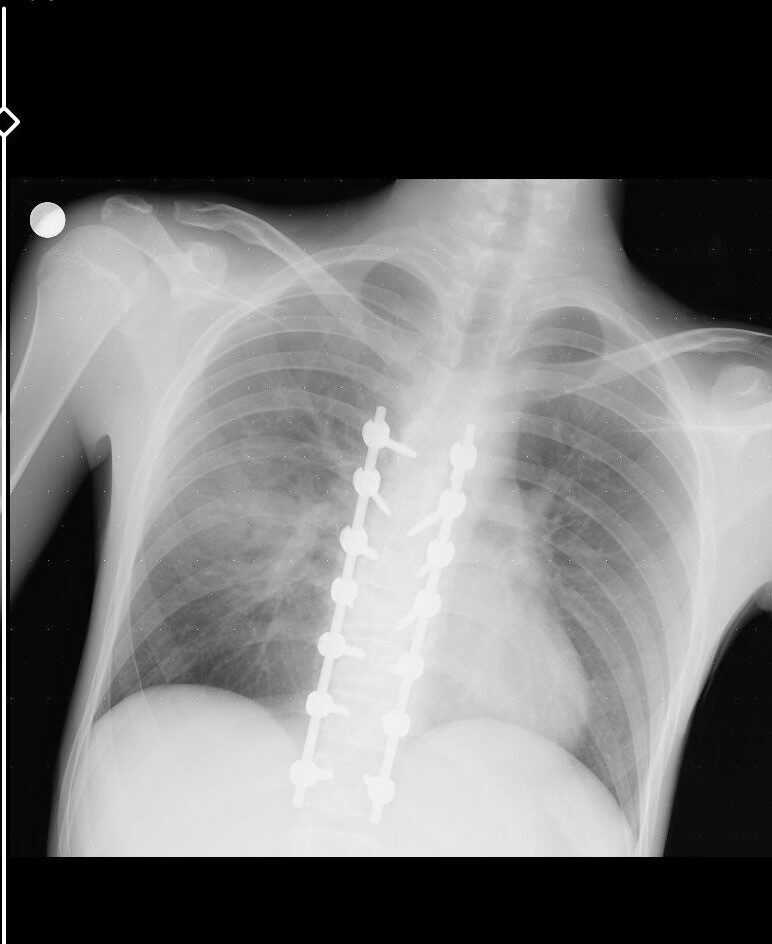

25 Eylül tarihinde Gündoğdu Mahallesi Cumhuriyet Bulvarı’nda gerçekleşen kazada, Birol T. yönetimindeki 34 HBF 007 plakalı otomobil ile Yusuf Gündoğmuş’un kullandığı 26 AIZ 906 plakalı motosiklet çarpıştı. Her iki sürücü de yaralanırken, motorcu Yusuf Gündoğmuş’un durumu oldukça kritikti. Kazanın ardından uzun bir süre Eskişehir Şehir Hastanesi’nin yoğun bakım ünitesinde tedavi gören genç adam, birden fazla operasyondan sonra hayata döndü. Ailesinin dua ve destekleriyle, tedavi süreci devam ediyor.

Yusuf Gündoğmuş’un tedavi sürecini detaylandıran babası, “Oğlum beş gün boyunca entübe edildi ve ciğerleriyle ilgili ciddi sorunlar yaşandı. Şükürler olsun, doktorlarımız sayesinde bu aşamayı atlattık. Oğlumun tedavisi ve sağlığı için sürekli dua ediyoruz,” dedi. Oğlunun sağlık durumu hakkında iyimser olduklarını belirten baba, yapılan operasyonların başarılı geçtiğini ifade etti.